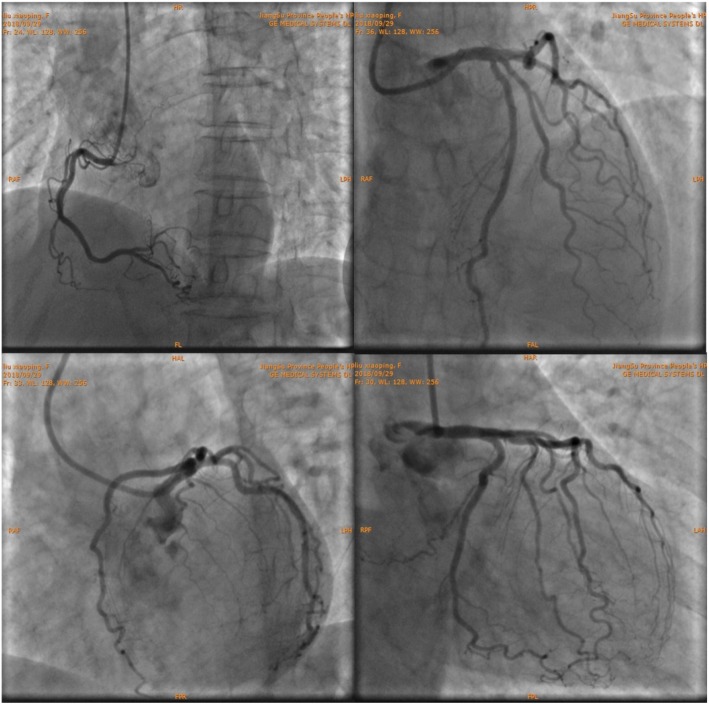

The patient had atypical angina symptoms, dynamic changes of ECGs and elevated cardiac biomarker. Her echocardiographic showed new significant abnormalities in the wall motion. Emergency CAG was performed and showed only approximate 30% stenosis in the left anterior descending (LAD) ostium and 40% stenosis in the first diagonal branch (Fig. 2), functional quantitative flow ratio (QFR) value for LAD was 0.96 (Fig. 3). Combined with the above history and test results, the diagnosis of MINOCA was ultimately made with the suspected causes of stress-induced coronary artery spasm and plaque disruption.

Fig. 2.

Images of coronary angiography. Approximate 30% stenosis in the left anterior descending (LAD) ostium and 40% stenosis in the first diagonal branch (D1)